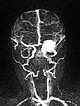

Dynamische, kontrastmittelunterstützte MR-Angiographie des Schädels und der hirnversorgenden Gefäße. In der arteriellen Phase 5 s später (B) bereits starkes Enhancement des Tumors am linken Auge.